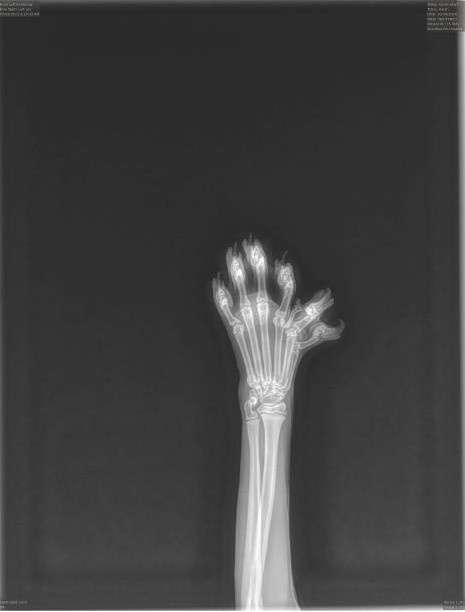

Radiographs (X-rays)

This safe and painless imaging technique uses controlled radiation to create detailed images of bones, joints, and some internal organs. X-rays are valuable for diagnosing fractures, dental problems, certain tumors, foreign objects, and other conditions.